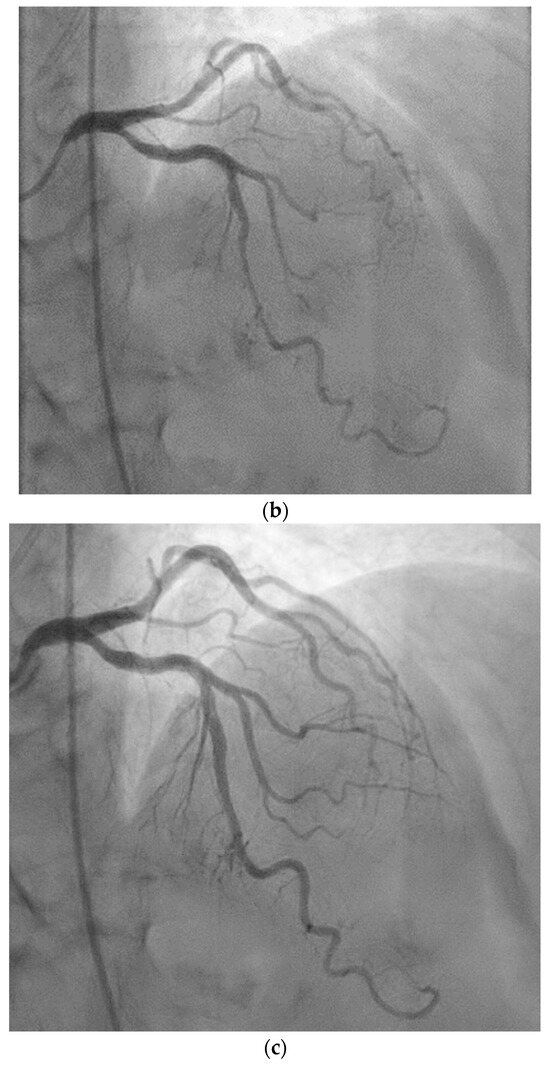

2. Case Presentation